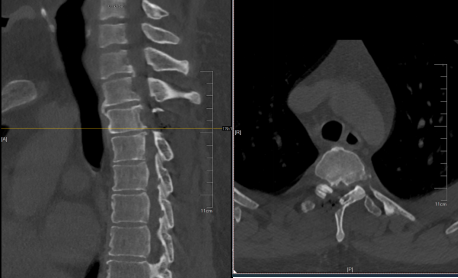

来自上海的32岁的王先生,身高196cm,体重160kg,BMI高达41.6(正常BMI一般在18.5-23.9),是一位名副其实的“巨人”。尽管身形魁梧,王先生却是一位优秀的长号手,毕业于音乐学院,拥有不少跟随他学习乐器的学生。然而,近一个多月王先生感到双下肢麻木。两周前症状迅速加重,双下肢的乏力、行走不稳,只能拄拐行走,不得不暂停授课。听闻姜为民主任的医术了得,王先生慕名前来就诊。CT及MR检查结果显示,王先生上胸椎T2-3水平黄韧带骨化伴严重的胸椎管狭窄。

术后复查胸椎CT显示,患者体内骨化块已完全切除,脊髓充分减压。考虑到患者体重较重且下肢肌力较弱,医生建议他暂缓下床行走。王先生下肢乏力的症状相较于术前已经有了明显的改善,他的脸上也露出了久违的笑容。术后仅4天,王先生便顺利出院,返回上海进一步休养。